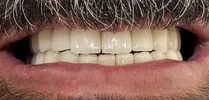

Zirconium Applications

Porcelain Applications

Laminate Veneer